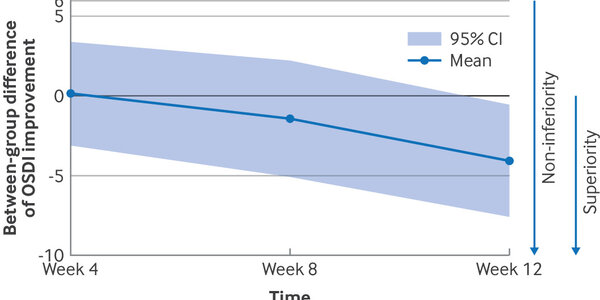

Over 50,000,000 Americans get subsidized or free health under the Affordable Care Act but that doesn't mean usage of preventive care increased across the board. Instead, a new analysis found that the...